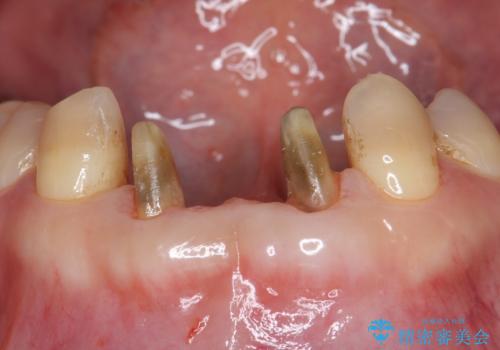

- 前歯のブリッジのやり替えをご希望されました。

かみ合わせが強く、以前入っていた保険治療のブリッジも前装が欠けてしまっていました。

セラミックも強い衝撃で欠けないわけではないため、強度のあるフルジルコニアクラウンでブリッジを作成しました。

フルジルコニアクラウンはやや白すぎるといった難点がありますが、今回は強度を優先することにしました。